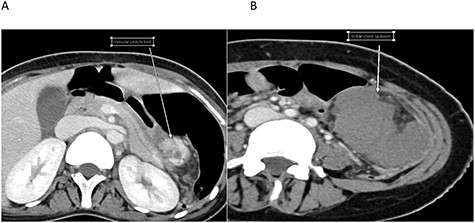

Her laboratory investigations were unremarkable aside from mild leukocytosis with a white cell count of 16 d/L. Computed tomography (CT) abdomen with intravenous contrast revealed twisted wandering dysmorphic spleen in the left mid abdomen with subsequent infarction (Fig. 1).

Cross-sectional images of the same patient at the time of infarction. A. Twisted pedicle. B. Infarcted WS.